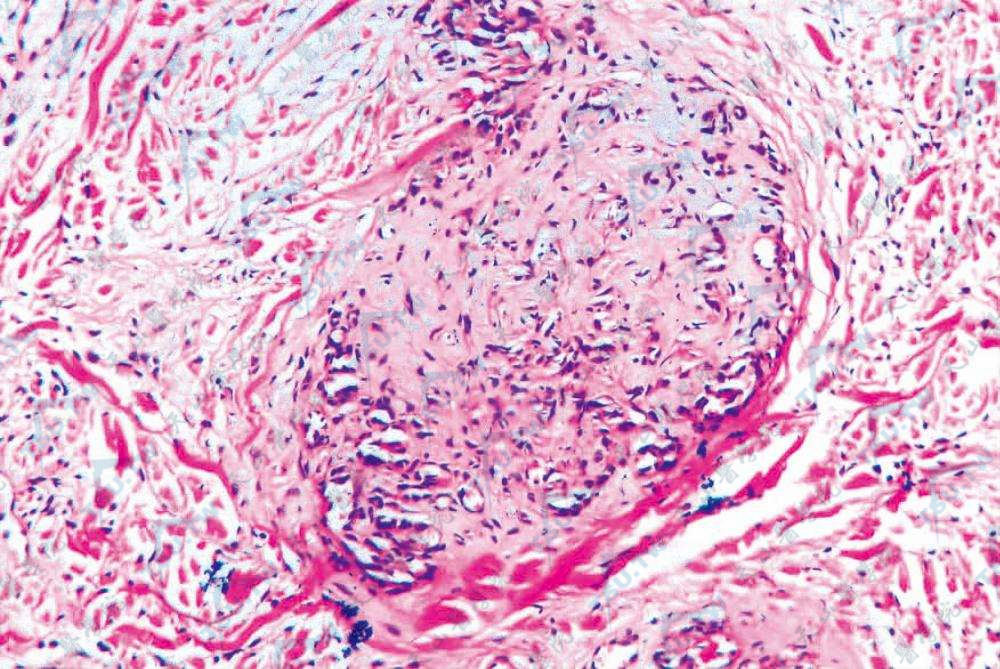

丛状血管瘤(Tufted Angioma)组织病理学改变

丛状血管瘤(Tufted Angioma)